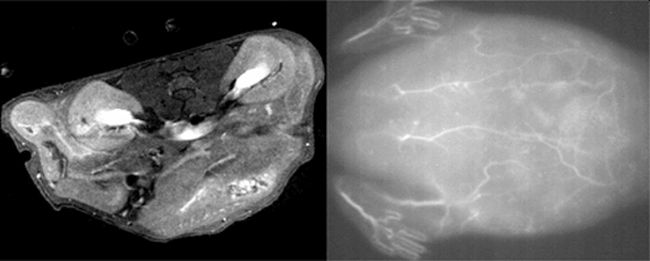

The scientists injected the nanoparticle solution into the tail veins of live mice and were able to obtain high quality MRI (L) and near-infrared fluorescence (R) scans of tissues and blood vessels.

The team conducted a series of tests to examine the properties of their nanoparticles. They found that they could be used for obtaining high-quality images of blood vessels in live mice using MRI and near-infrared fluorescence imaging techniques. Further tests showed the nanoparticles exhibited minimal toxicity on mouse fibroblast cells when used in low concentrations. They also have a short half-life, meaning they would be cleared relatively quickly from the body, making them safe for clinical use.